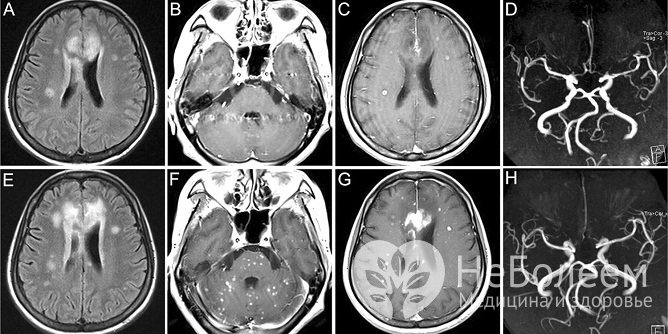

Один из методов диагностики атеросклероза сосудов головного мозга – МРТ головного мозгаТакже при диагностике атеросклероза сосудов головного мозга проводится лабораторно-инструментальное обследование, включающее: